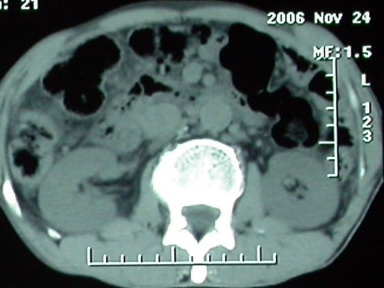

门脉主干及肠系膜上静脉近端明显增粗,尤其前者呈等低混杂密度,增强后周围见轻度环形强化。明显占位效应。肝内外胆管见大量气体影。胆囊明显增大。

考虑:1、门脉栓塞; 2、肝内外胆管积气。

ct表现:1,胰腺钩突后方肿块,不均强化,中心密度低,钩突及门静脉前移。2:肝右后叶不均强化灶,突出肝表面,3:胆囊明显增大,肝内胆管及肝总管内积气。4:腹腔内少量积液。

考虑:1:胆囊炎,胆管炎。2:肝癌合并腹腔内转移灶,腹水。

肝脏尾状叶肝癌(沿肝十二指肠韧带向下韧带内生长,门腔间隙外压增大),大结节性肝硬化,胆囊积脓,胆道感染。术中见肝外胆道2cm直径,肿瘤向前压迫胆管至扁平状态。